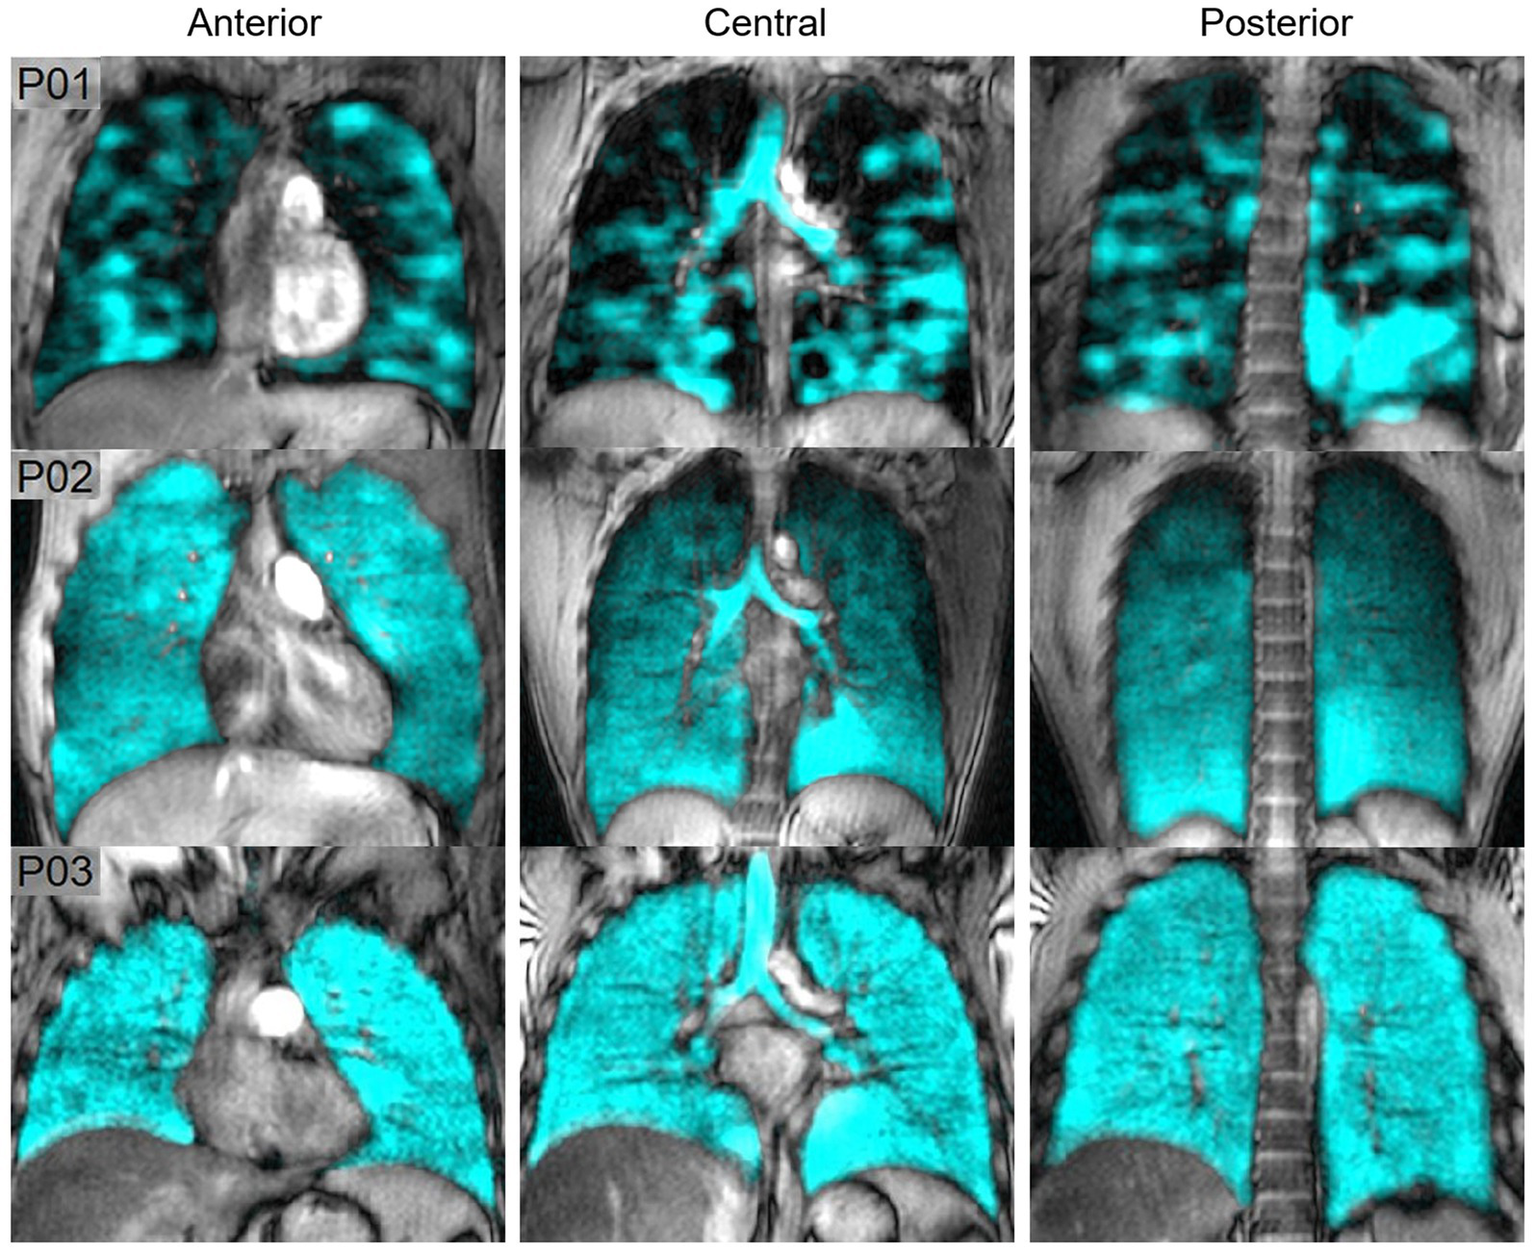

Figure 8 shows hyperpolarized 129Xe MRI ventilation (cyan) co-registered with anatomical 1H MRI (greyscale) for one participant with EVALI, one asymptomatic e-cigarette user and one healthy participant; all images were acquired by the authors’ group. The participant with EVALI demonstrates a heterogenous ventilation pattern with multiple ventilation defects, represented as black regions, throughout the entire lung. In contrast, the asymptomatic e-cigarette user demonstrates a relatively homogenous ventilation pattern with evidence of small, peripheral ventilation defects in the lung apices. Finally, the healthy participant has a homogenous ventilation distribution with no ventilation defects.

Figure 8

Hyperpolarized 129Xe MR ventilation imaging in chronic vapers and similar-aged healthy volunteer. Anterior, central, and posterior coronal slices of 129Xe ventilation (cyan) co-registered with anatomical 1H (greyscale) MRI. All images were acquired by the authors’ group. P01 is an 18 years-old male with severe bronchiolitis and respiratory failure caused by e-cigarette use, 1 month post discharge after a 6 months history of vaping (VDP = 21%). P02 is a 29 years-old male with a 2.5 years history of vaping nicotine (3/4 pods daily) (VDP = 4.7%). P03 is a 22 years-old male with no history of chronic respiratory abnormalities, vaping or combustible cigarette use (VDP = 1.5%).

Two studies compared the acute effects of e-cigarette use on ventilation. In the first, alveolar ventilation and ventilation heterogeneity in asymptomatic e-cigarette users were similar to healthy controls prior to exposure, however both measurements worsened following exposure to vaping in e-cigarette users (107). In contrast, while the second study observed a nominal increase in ventilation impairment post-exposure, this change was not statistically significant (108). In a similar manner, the 129Xe MRI ventilation pattern of a patient recovering from EVALI was highly abnormal and dissimilar to the patterns previously observed in either asthma or COPD (61). Furthermore, these ventilation abnormalities persisted for at least 8 months (61).